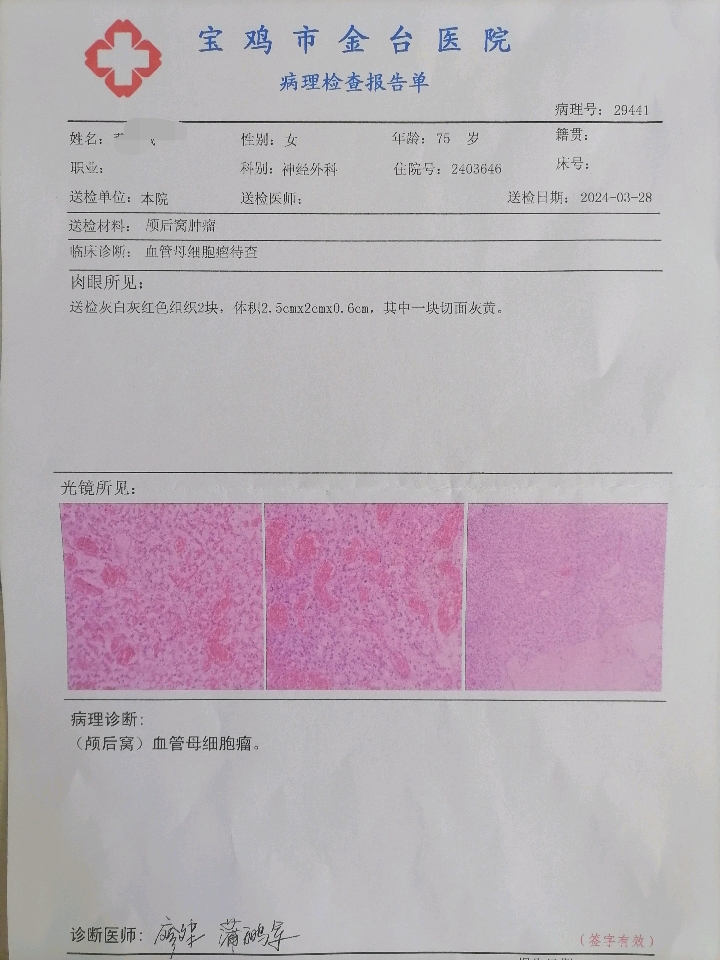

今天为大家分享的是宝鸡市金台医院神经外科高振辉团队带来的一例枕大孔区巨大血管母细胞瘤病例

患者董某某,女,75岁

主诉:晕厥半天

初步诊断:枕大孔区占位性病变 血管母细胞瘤

术后患者一般情况良好,无新发神经功能障碍,共济运动失调较前好转。

讨论: